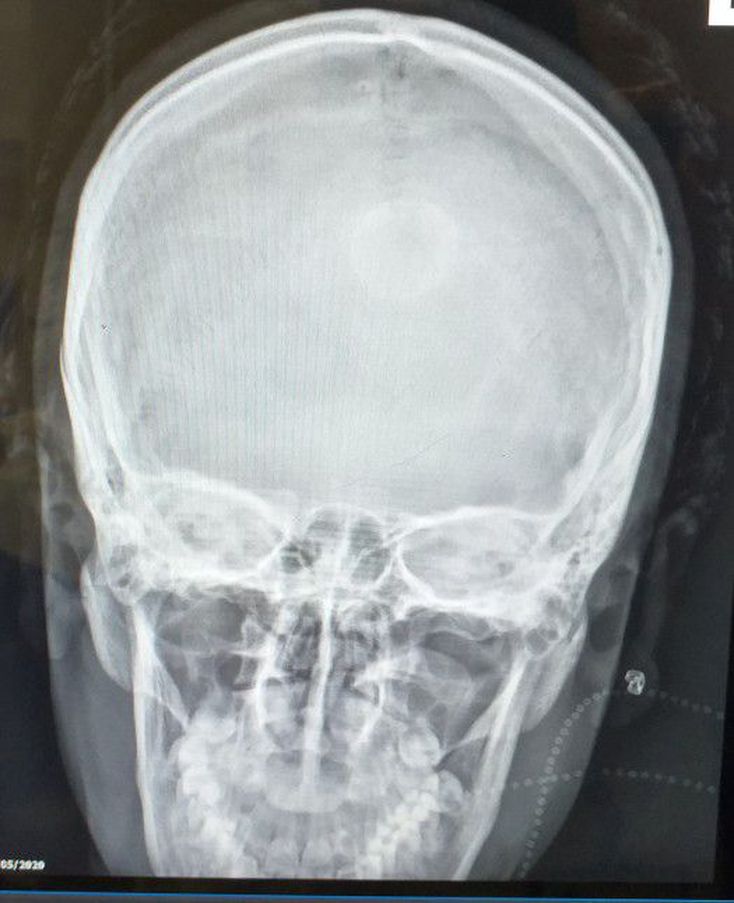

What is your diagnosis?

Xray

Skull

Earache

Skull Xray

A girl with earring broken in her ear.